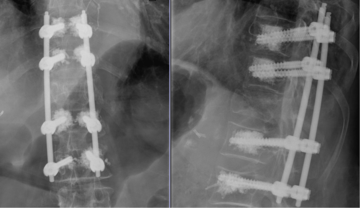

Der Wirbelkörperersatz wird bei instabilen Brüchen angewendet, die häufig aus mehreren Bruchstücken bestehen und ein Kippen der Wirbelsäule nach vorne zur Folge haben können. In der Regel wird zuerst eine hintere Stabilisierung durchgeführt, um den zerstörten Wirbelkörper von der Seite her zu entfernen. Der gebrochene Wirbelkörper wird dann durch einen sogenannten „Cage“, einen künstlichen Wirbelkörper aus Titan oder einer hochwertigen Legierungen, ersetzt.

Ziel dieser Operation ist es, eine dauerhafte Festigkeit und knöcherne Verbindung zwischen den benachbarten Wirbeln zu erreichen, um eine belastungsstabile Wirbelsäule wiederherzustellen.

Hintere offene Stabilisierung durch ein Schrauben/Stab-System und Wirbelkörperersatz bei Bruch des 4. Lendenwirbelkörpers.